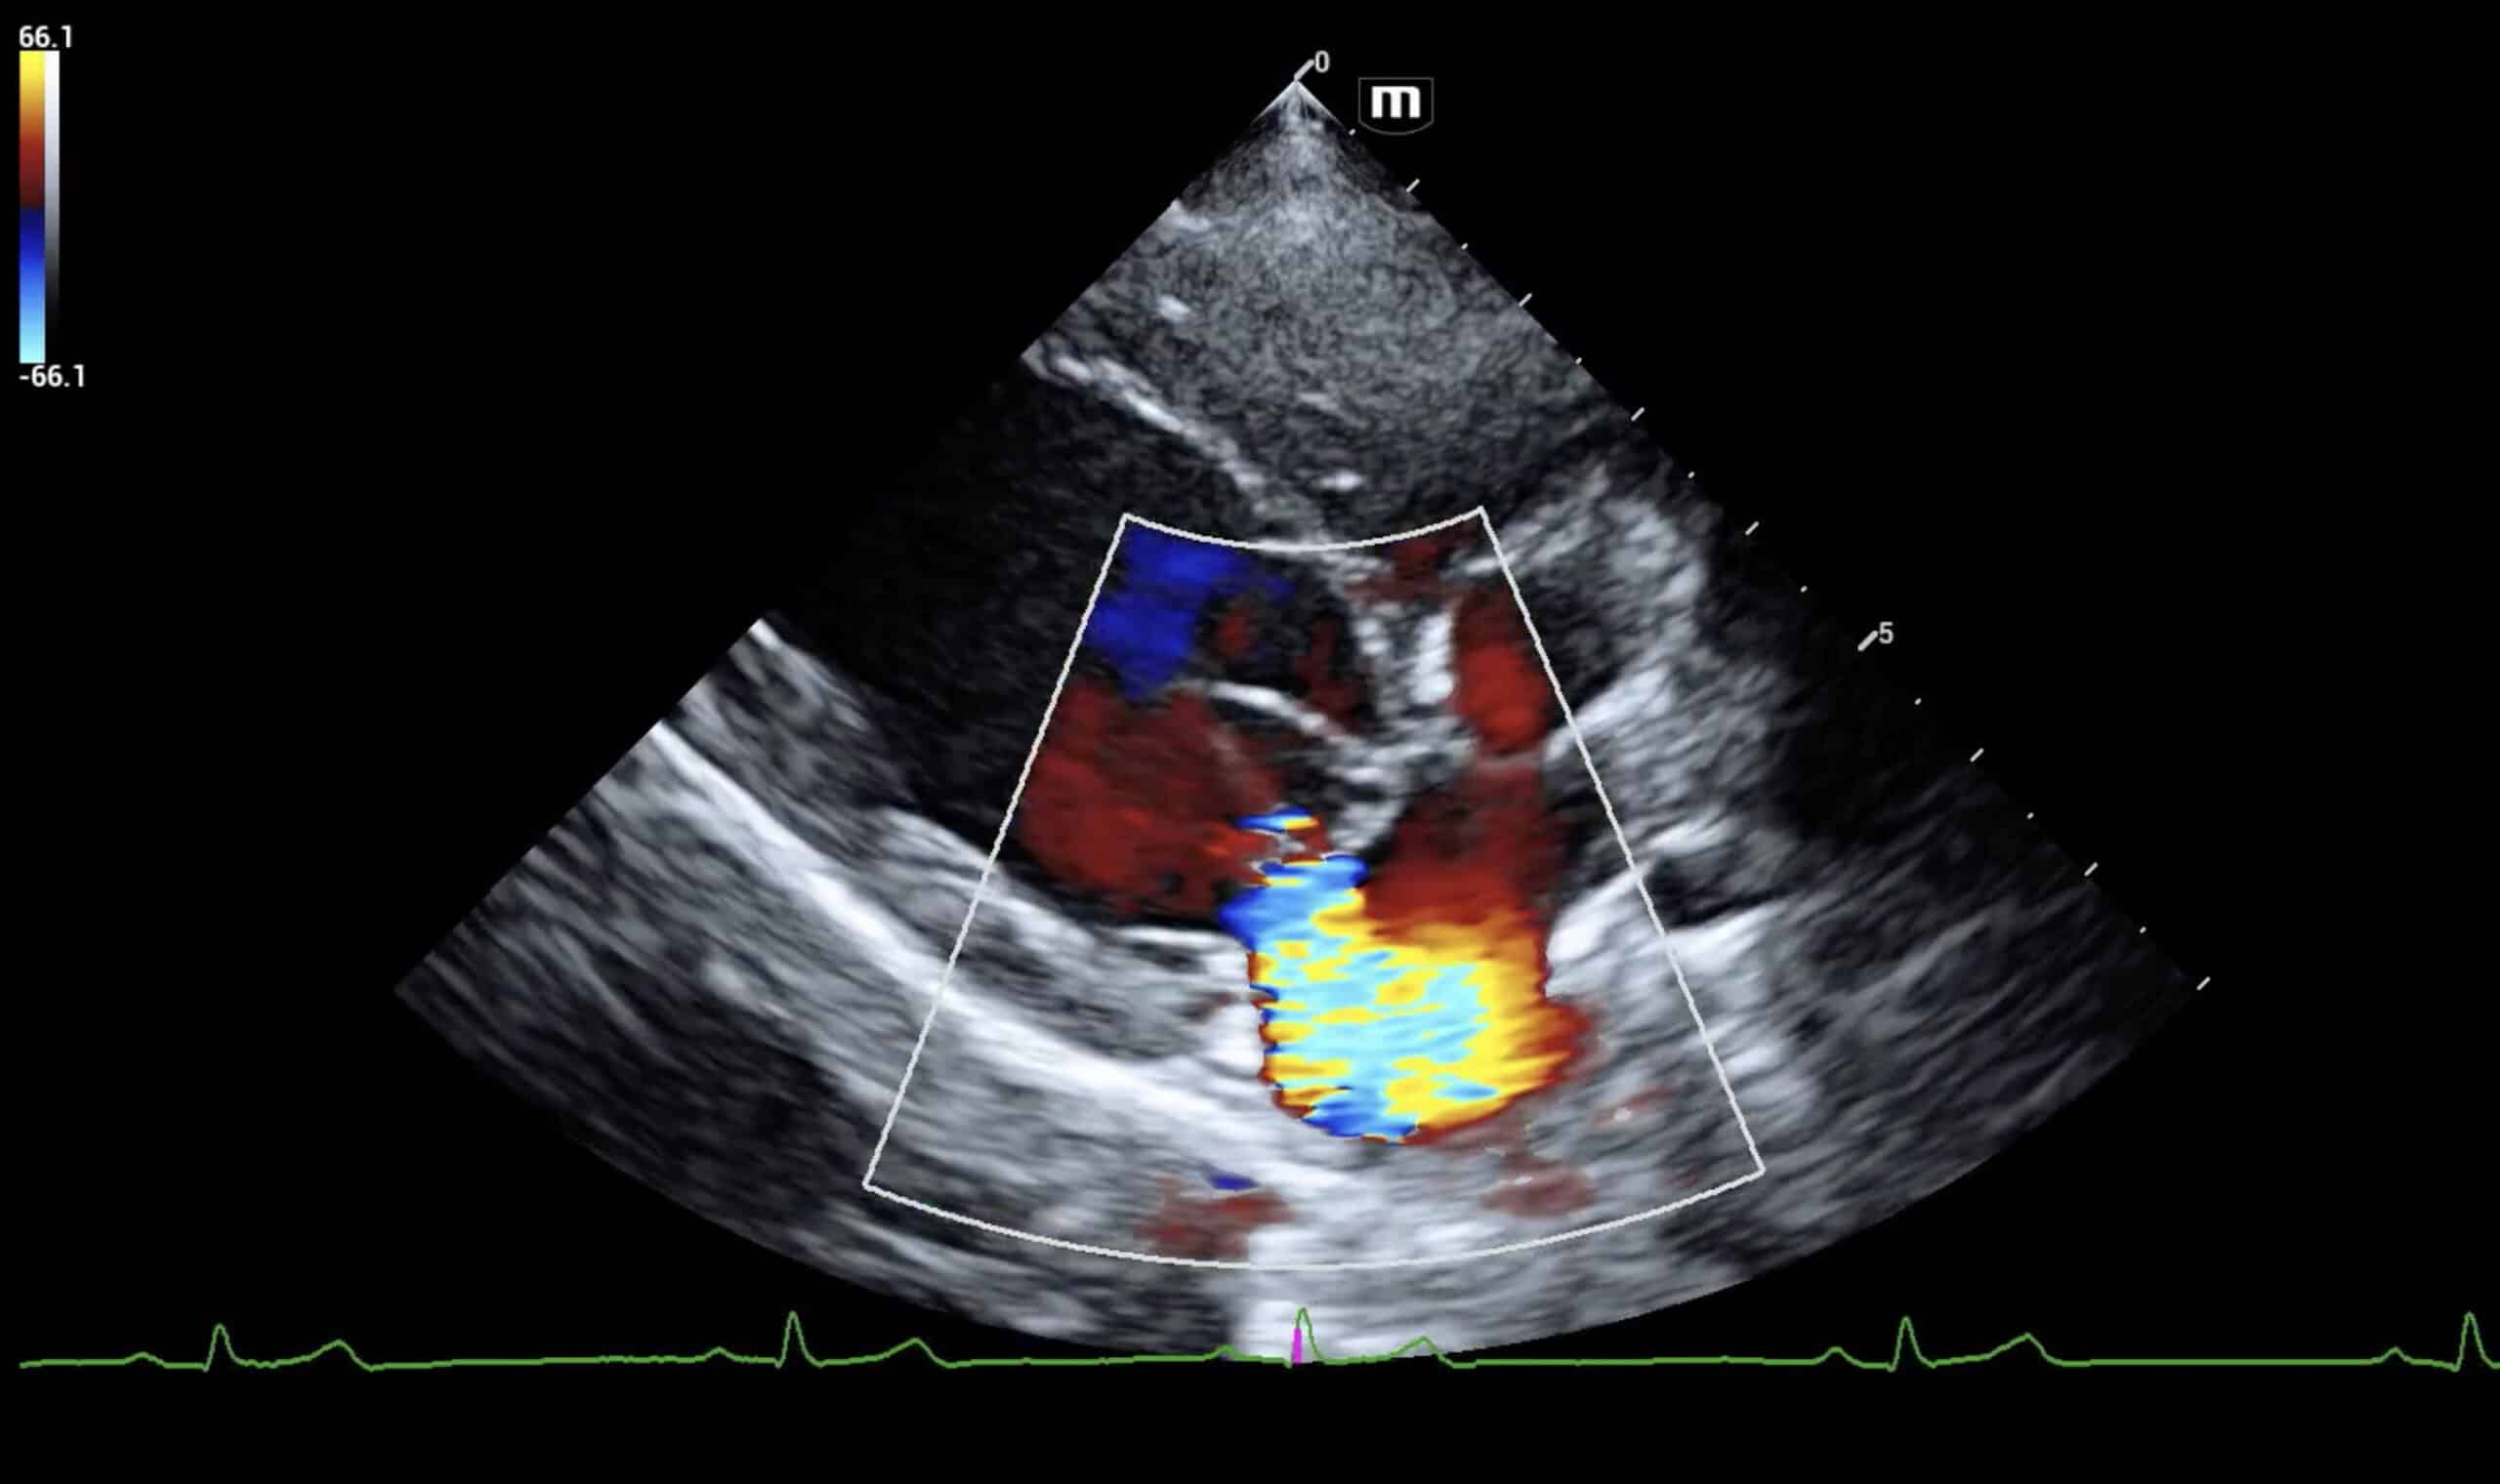

We provide in-clinic veterinary echocardiograms and ultrasounds, delivering advanced imaging directly to your clinic. Our ARDMS-credentialed sonographers use state-of-the-art ultrasound equipment to perform detailed, non-invasive assessments. This mobile service eliminates the need for external referrals, reduces stress for pets and owners, and supports faster, more accurate diagnoses. Whether for symptomatic patients or routine screenings, our echocardiograms and abdominal ultrasounds help veterinarians make informed, timely treatment decisions—all without leaving the clinic.

Echocardiograms

Learn more about our echocardiograms